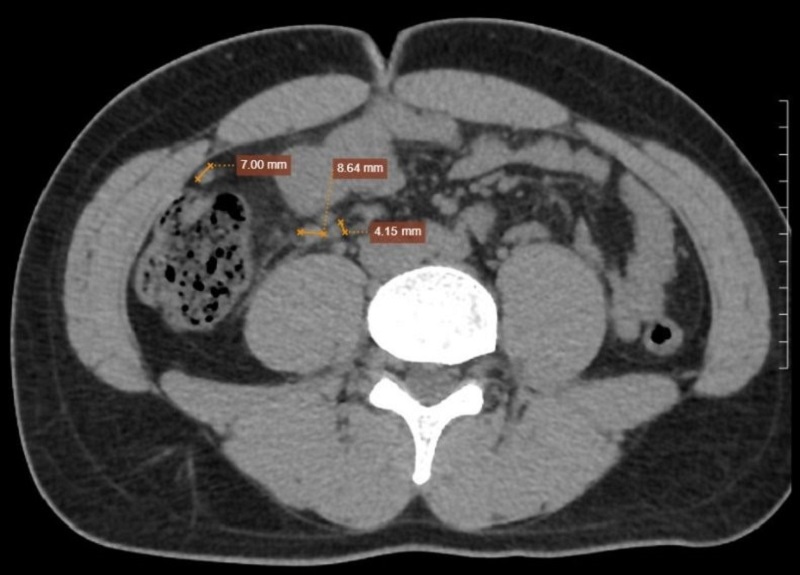

Những hình ảnh bất thường của bệnh nhân ghi nhận trên phim chụp CT Scanner ổ bụng

Trước sự không tương xứng giữa lâm sàng và siêu âm, bệnh nhân được chỉ định chụp CT Scanner ổ bụng. Kết quả ghi nhận ruột thừa vị trí góc manh tràng, đường kính gốc 7.7mm, thân 8.1mm, ngọn 7.2mm (đoạn ngọn quay ngược lại phía gốc ruột thừa tạo thành hình tròn), trong lòng chứa dịch, thành còn liên tục, ngấm thuốc sau tiêm. Hồi tràng thành dày nhẹ, thâm nhiễm mỡ xung quanh. Mạc treo lân cận có vài hạch, đường kính ngang lớn nhất 8.6mm. Từ đó, chẩn đoán xác định viêm ruột thừa cấp được đưa ra và bệnh nhân được chỉ định phẫu thuật kịp thời.